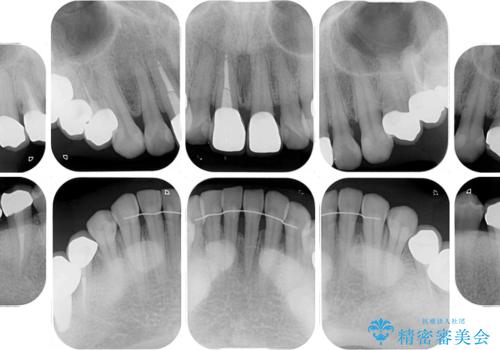

- 右下の欠損部の治療を希望して来院された患者様です。

部分矯正を行った後にインプラント埋入と手前の歯の根管治療を行い、その後補綴治療を行うこととしました。

治療途中より、上の歯や反対側の銀歯、上顎前歯の色合いや下顎前歯のデコボコが気になってきたため、全てを治療することとしました。

仕事が多忙な方で、来院間隔が開いてしまうことが多く、治療期間はかかりましたが、来院回数は最小限で終えることができました。